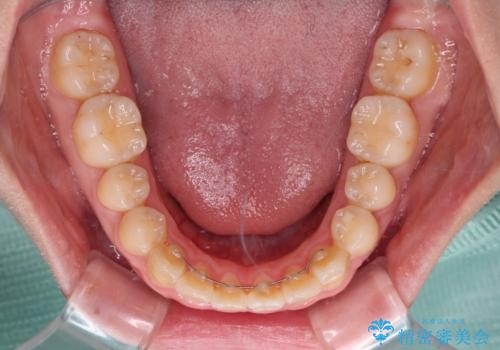

- 中学生の頃にぶつけた前歯に不格好なクラウンが装着されており、出っ歯な印象になっていることを気にして来院された患者様です。

ぶつけてしまった歯は保存が困難な状況であったので抜歯をし、ワイヤー矯正により歯列を整えつつ前歯の突出感を解消することとしました。

矯正治療後にはインプラント補綴治療を行うこととしました。